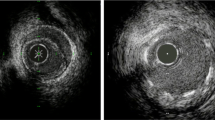

Intravascular ultrasound (IVUS) has been employed for several decades and revolutionized the ability to assess the efficacy of percutaneous coronary intervention (PCI) (e.g., stent expansion) and complications of PCI (e.g., arterial wall dissection, tissue prolapse), and characterize atherosclerosis (e.g., plaque calcification, plaque burden, and severity of left main CAD) and vessel geometry (Fig. 1). More recently, intracoronary optical coherence tomography (OCT) has emerged to overcome some limitations of IVUS by providing very high–resolution images (ten times higher than conventional IVUS, five times higher than high-definition (HD) IVUS), allowing spectacular visualization of stent struts and arterial wall dissections, and the ability to assess plaque composition of the fibrous cap, lipid, calcium and calcified nodules, and thrombus. Mechanisms of stent failure such as fracture, deformation, or recoil are also better illuminated by OCT.

Comparison of optical coherence tomography (OCT) and intravascular ultrasound (IVUS) from the same lesions. A) Lumen area measured 8.40 mm2 by OCT and B) 8.83 mm2 by IVUS. External elastic membrane (EEL) diameter (yellow double arrowhead) measured 3.86 mm by OCT and 4.09 mm by IVUS. Lumen diameter (white double arrowhead) measured 3.28 mm by OCT and 3.54 mm by IVUS. Magnified details of A) and B) are shown in A′) and A″) for OCT and in B′) and B″) for IVUS (EEL: red dotted line, internal elastic lamina: yellow dotted line, lumen surface: blue dotted line. C) EEL border is not visualized with OCT at the lesion (white arrowheads) due to plaque attenuation and limited penetration depth, but clearly visualized by D) IVUS (white double head arrows, 5.2 and 4.4 mm). E) Stent area measured 8.10 mm2 by OCT and F) 8.24 mm2 by IVUS. White arrow indicates stent strut. Reprinted from Maehara et al.40 with permission from Elsevier

Advances in OCT Imaging